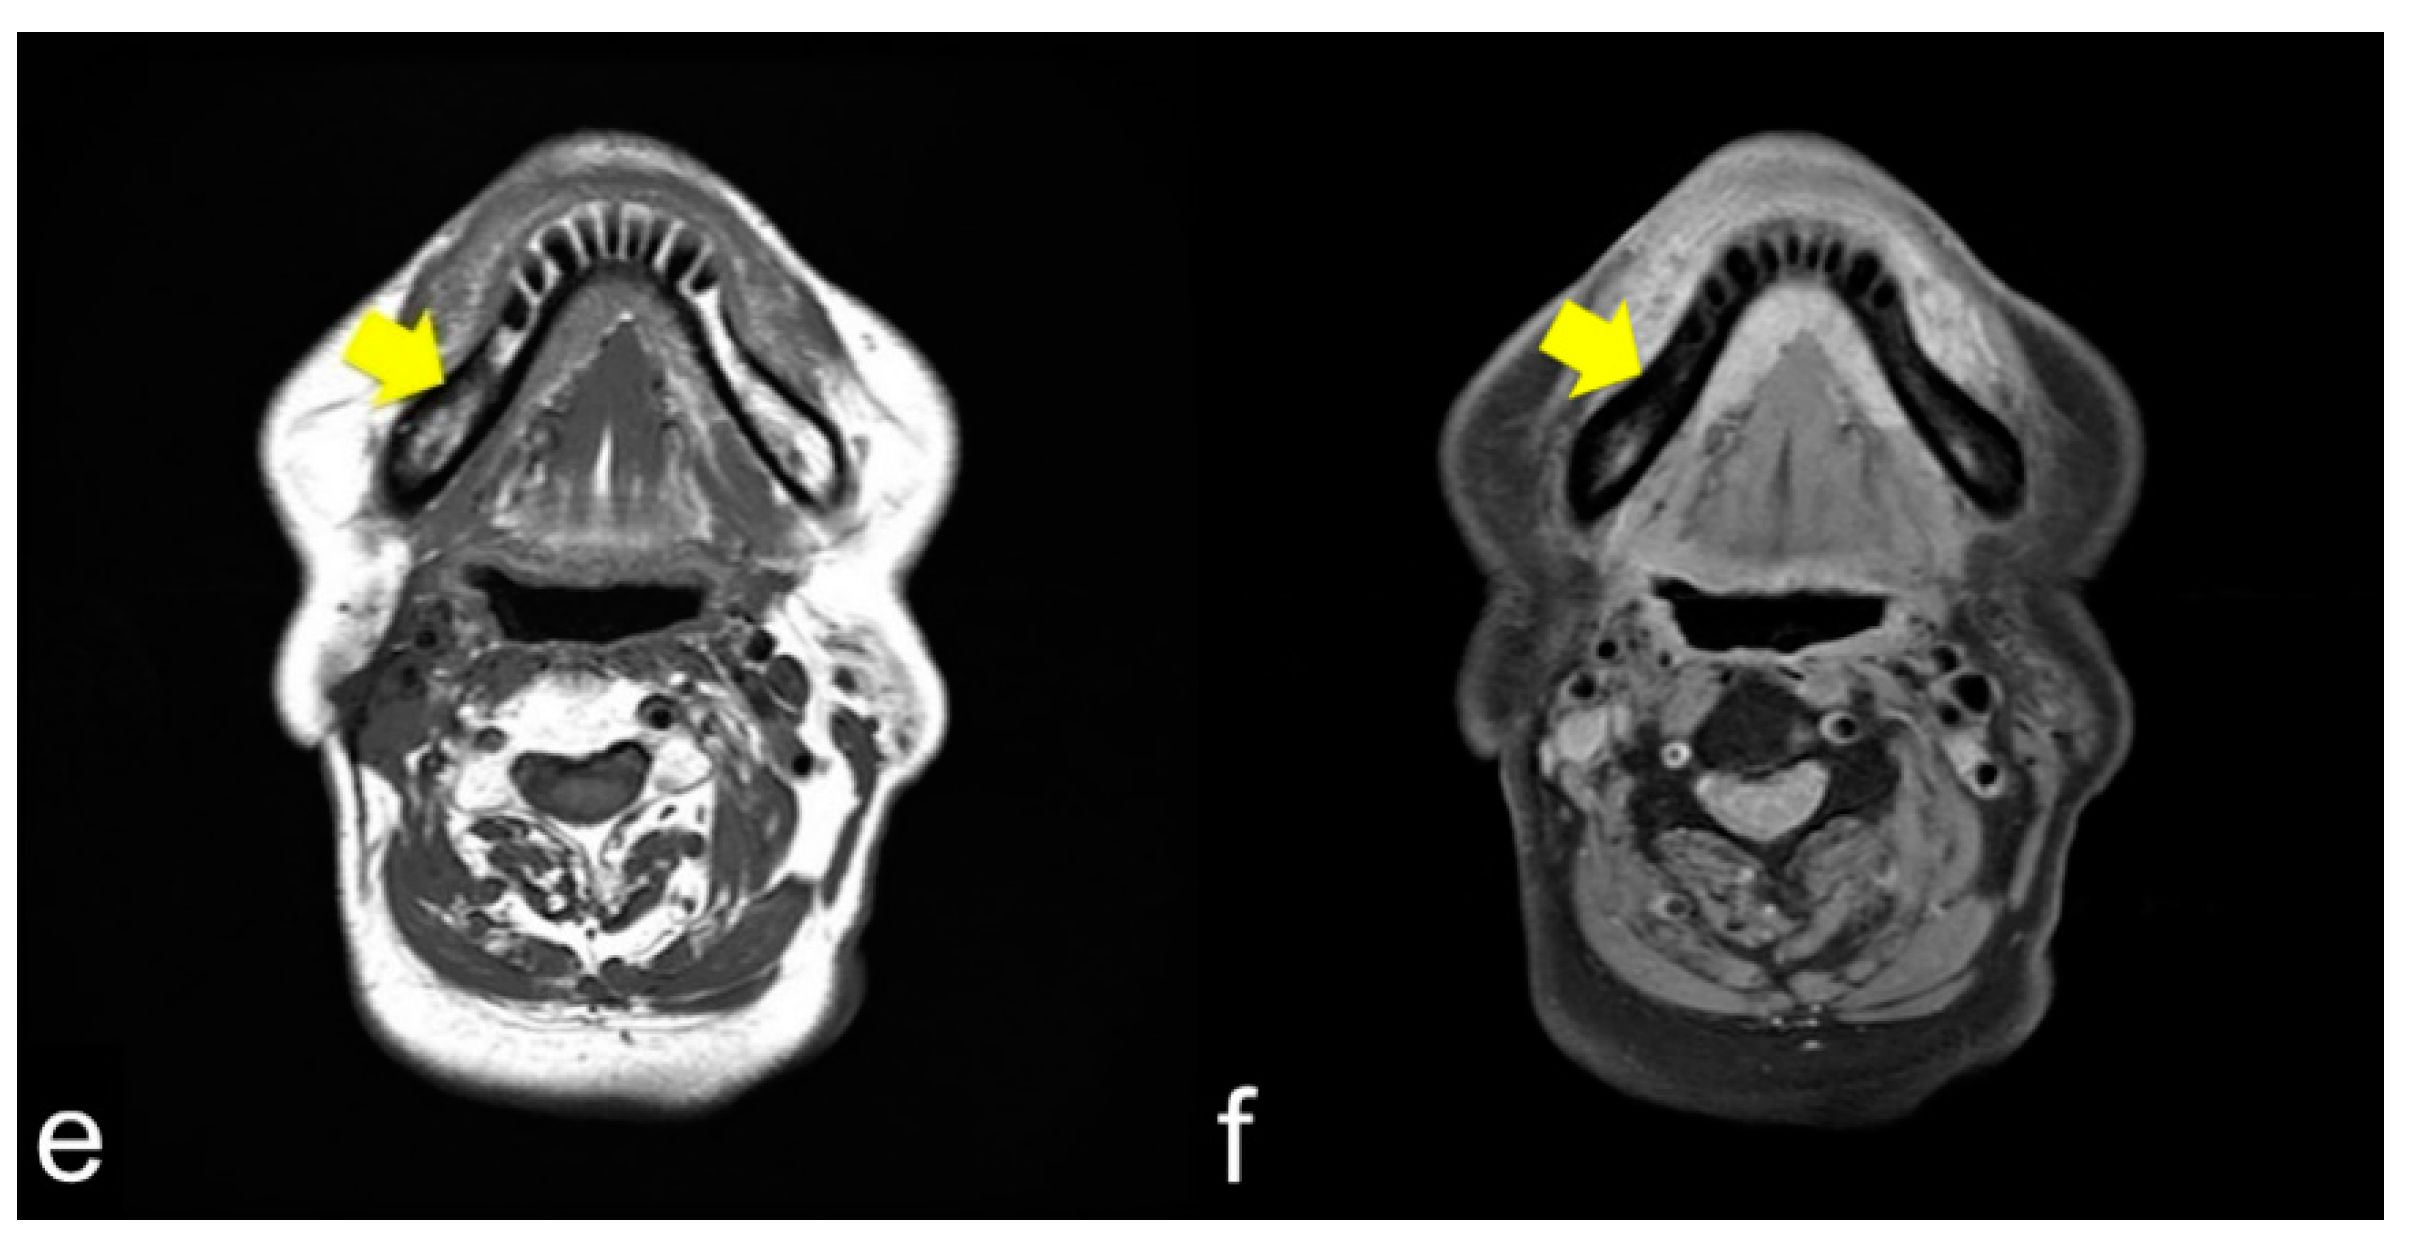

MRI showed that the damage to the bone marrow by RT continued even after the long-term asymptomatic phase. Even if there are no clinical symptoms of ORN, the bone marrow is considered abnormal for a long time after RT. Considering the CT images, the consolidated bone region would have devitalized or reduced vitality, possibly fibrosis with lower blood supply. Partial bone resorption and reactive fibrosis showed a mixed image of bone consolidation (low intensities on T1 WI and heterogeneous hyper-intensities on T2 WI), as Kaneda has previously suggested [13,21]. Moreover, the homogeneous hyper-intensities of T2 WI may be mild bone marrow inflammation considering the clinical symptoms of ORN. From a clinical point of view, tooth extraction within the radiation field should be performed with caution at any time after RT. If abnormal bone marrow is invaded by triggers, the symptoms of ORN would change from the chronic inflammation phase to the acute inflammation phase. Tooth extraction before RT is recommended, but it does not prevent ORN; the essence of ORN is devitalized bone. Considering soft tissue, CT and MRI often show inflammation in the surrounding masticatory muscles, and MRI can confirm the inflammatory symptoms around the masticatory muscles [39]. These symptoms are related to trismus. As the ORN stage progressed, chronic trismus increased, which indicated that inflammation from the bone marrow extended beyond the cortical bone to the inferior border of the mandible and into the surrounding soft tissue. Trismus was observed with cortical disruption on CT (Figure 3a,c) and abnormal T2 signal intensity, enhancement, and thickening of the masseter and pterygoid muscles (Figure 3b,d). In such a condition, antibiotics only cause acute inflammation in the chronic phase. The degree of trismus would improve with surgical resection of the necrotic bone, however, with only conservative treatments, it is unclear whether trismus can be improved.

Figure 3.

(a,b) Axial CT and T2 WI magnetic resonance images show cortical bone disruption and abnormal signal intensity in the masticatory muscle; (c,d) Coronal images also show chronic inflammation, particularly in the medial pterygoid muscle. Chronic inflammation in the masticatory muscles results in trismus.